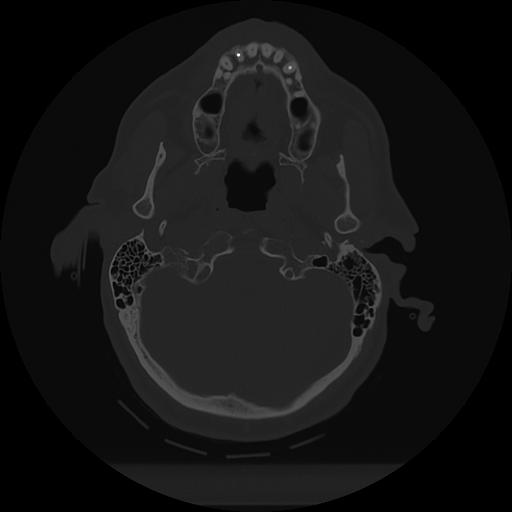

11 HUESO,,Axial,2.0,HUESO,,